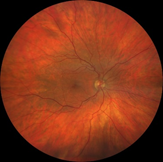

Dilated fundus examination revealed relatively normal fundus with cup-to-disc (C/D) ratio of 0.30 round OD (Figure 1A). The fundus photo of the left eye showed a pale posterior pole with swollen optic nerve head and macular cherry spot (Figure 1B). Ocular coherent tomography (OCT) macular cube scans showed a representative slice of normal retinal layers through the macula OD (Figure 2A), and a pigmented epithelial detachment and disrupted retinal layers extending temporally from the optic nerve head (ONH) OS (Figure 2B). Additionally, Figure 3 and Figure 4 showed the OCT optic disc cube 200x200 scan with swollen ONH OS, and OCT macular cube 512x128 scan with detached retinal layers OS, respectively.

Figure 1A Fundus photo of patient’s retina showing relatively normal fundus OD.

Figure 1B Fundus photo of patient’s retina showing pale posterior pole with swollen optic nerve head and macular.

This case report is rare because the patient suffered both from an acute CRAO and PED after a prolonged coughing episode. His ONH was swollen with indistinct margin, and the posterior pole was pale with a typical fovea cherry spot (Figure 1B). Extensive swelling of inner retina and PED extending from the ONH were apparent on OCT imaging (Figure 2B). When he showed up to the UCC the next day, it had already passed the critical window of 6 hours so not much could be done ocularly to reverse the retinal damages in the left eye. The patient was referred to a local retinal specialist who then sent the patient to the emergency department for a more extensive stroke work up at a local hospital emergency department. There, he was found to have left proximal ICA stenosis, chronic atrial fibrillation, interstitial lung disease, chronic GERD, and severe shoulder arthritis. Then, he was discharged in stable condition and scheduled to have continued care with retinal specialist, PCP, pulmonologist and cardiologist.